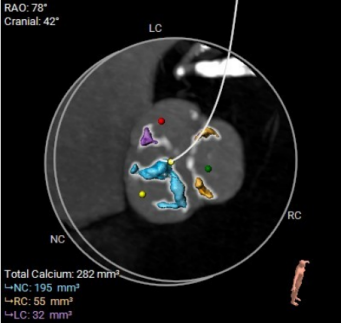

▲术前CT评估

团队没有贸然手术,而是先对庄爷爷进行了全面细致的术前评估:通过 CT 精准测量主动脉根部、冠脉高度、入路血管等关键数据,结合超声心动图评估心脏功能,最终确定为他实施 TAVR 微创手术。